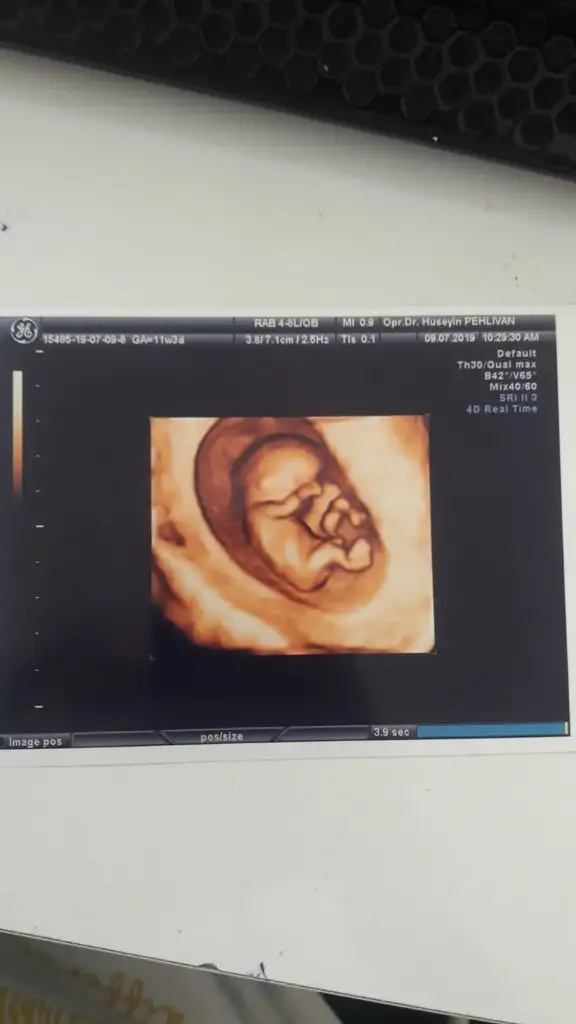

Bu usg saha öncede yorumladım sanki erkek gibiYorumlarinizi alabilir miyim? 12+4 teki usg miz

Kız canım zaten nub olmaz 13+4 haftada ya pıtış ya pipi olur bu bebek bence kız dr tahmin etmediniMerhaba bugün devlet hastanesinde kontolüm vardı cinsiyet için erken dedi burda 13+4 yeniden cinsiyet tahmin edebilir misiniz ?

Erkek gibi geldi banaCocoChanelmademoiselle Ikra meyra M mely15 sizlerin yorumunu merak ediyorum bugün ki ultrason görüntüleri

15 haftadasınız dr yorum yapmadımı 11 yada 12 hafta olmalı nub içinCocoChanelmademoiselle Ikra meyra M mely15 sizlerin yorumunu merak ediyorum bugün ki ultrason görüntüleri